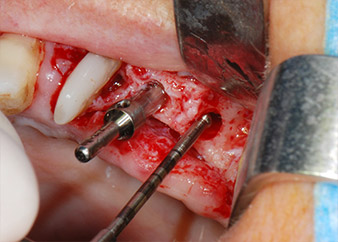

Prior to implant placement, infected tissue was removed from the alveolar bone in the implant site and around the abutment teeth with an insert originally designed for bone shaping and collecting bone chips (Piezomed, insert B5) (Figs. 6 and 7).

IImplant beds were prepared at sites 25 and 26 with rotary instruments, used in a contra-angle handpiece with a 20 : 1 transmission ratio with an updated powerful implant motor (Implantmed, W&H) (Fig. 8).